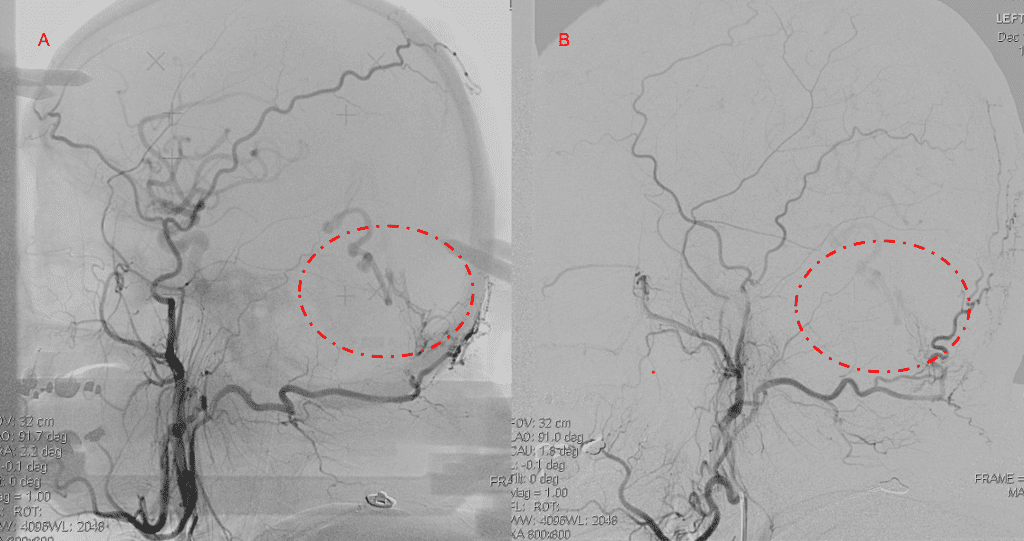

Over the 12 to 18 months, she continued to remain event-free and maintain her active independent lifestyle. Delayed angiography over that period confirmed complete obliteration of the Left ECA and Vertebral Artery shunts with near complete obliteration of the Right ECA shunts (Figure 7).

Figure 7. 12 mos follow-up angiograms confirm complete obliteration of the left ECA and Vertebral Supply to the AVM, with a small late-filling component from the right Occipital artery that is markedly Reduced in size and flow (top row). Near complete resolution of the aneurysm and hematoma Is observed on 16 mos post Gamma Knife MRI (bottom row).